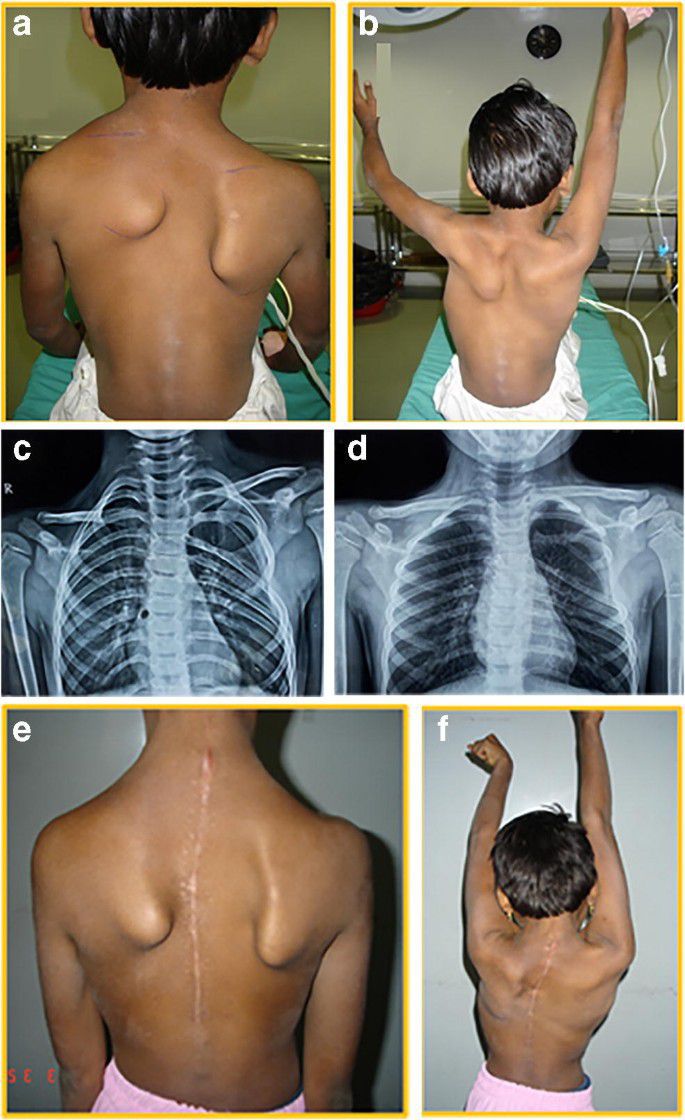

Sprengel shoulder is a congenital deformity of the scapula characterized abnormal connection between the cervical spine and the scapula. The connection may be formed by omovertebral process, fibrous band, or a bony bar. The individual presents with higher, rotated, and smaller scapula. The patient may have other associated conditions such as cardiovascular disorders, scoliosis, or abnormalities of thorax, thoracic or cervical spine. Reference: Bailey and Love's Short Practice of Surgery Image via: https://link.springer.com/article/10.1007/s00264-020-04560-7